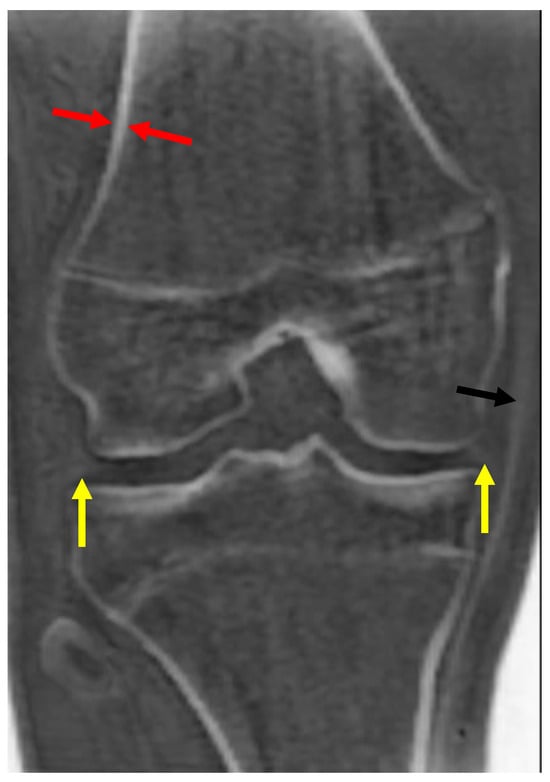

Imaging with zTE captures the signal from cortical bone and fascia, which still remain low-signal compared to other tissues due to their low mobile proton densities [21,22]. Long T2* tissues are high-signal on these images but show little contrast between them. Following bias correction and intensity normalization, these images can be displayed with an inverted gray scale, so that the cortical bone and fascia appear high-signal (bright) and long T2* tissues appear low-signal (dark). Most currently available commercial MR scanners include this option for imaging cortical bone (Figure 1).

Figure 1.

Coronal zTE image of the knee displayed with an inverted gray scale. Cortical bone (red arrow) is bright. Other short T2 tissues, such as the medial collateral ligament (black arrow) and the menisci (yellow arrows), are also bright, but less so than the cortical bone.